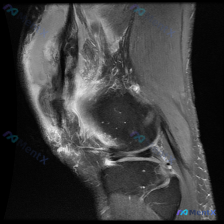

都在说半月板异常,MRI却提示另有病因?这个膝关节影像有点容易走偏

刚看到这张膝关节MRI的读片请求,主诉方向是考虑半月板异常,整理一下完整的影像观察和分析思路,和大家一起讨论。

这是一张膝关节矢状位T2加权MRI,序列特点是:关节液、水肿、炎症呈高信号(亮白色),皮质骨和韧带肌腱呈低信号(黑色),骨髓肌肉为中等信号。

- 半月板(就是大家一开始关注的结构):在当前层面半月板保持正常三角形楔形形态,没有明确截断、移位,内部也没有看到贯穿关节面的典型高信号,没有发现支持半月板撕裂的直接证据,用户假设的半月板异常和当前影像表现不符

- 髌下脂肪垫(Hoffa脂肪垫):前方髌下区域呈现大范围异常高信号,提示非常显著的水肿/炎症反应

- 膝关节前方软组织:髌韧带、股四头肌腱周围软组织信号增高,提示存在创伤或炎症改变

- 交叉韧带:走形连续性尚可辨认,但周围信号偏杂乱

- 骨髓信号:股骨远端、胫骨近端骨髓腔没有看到明确局灶性骨挫伤的斑片状高信号

- 关节:可见中等量关节积液,主要分布在髌上囊和关节间隙周围

一开始大家都奔着半月板异常去,但读片首先要尊重影像事实:半月板本身没看到明确异常,反而膝关节前室有非常显著的弥漫性炎性改变,这个反差是这个病例最关键的点,诊断思路必须从「结构性半月板损伤」转向「炎性/软组织病变」。